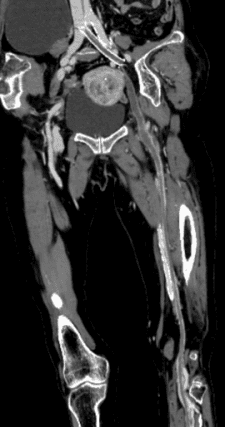

患者是一位88岁的老年女性,体重仅45公斤,因“左下肢突发肿胀3天”紧急入院。其病史极为复杂:11年前曾患DVT,2014年接受了下腔静脉滤器植入及左髂静脉支架植入术,2016年又因支架内闭塞接受了血管再通手术,同时还患有高血压和冠心病。入院检查结果显示D2聚体水平飙升至11.37μg/mL,影像学检查明确显示左下肢深静脉系统自髂总静脉至胫前后静脉广泛血栓形成并部分闭塞,左髂内静脉疑已闭塞,下腔静脉滤器在位,甚至提示存在左下肺肺动脉小分支栓塞的可能。患者超高龄、基础疾病缠身、既往多次手术导致血管条件极差、血栓负荷巨大且新旧混杂,治疗面临前所未有的风险和挑战。

血栓清除后,造影显示患者左髂静脉原支架内存在严重狭窄——这是既往手术遗留的复杂难题。团队迅速制定应变方案,先后使用不同规格球囊对狭窄部位进行充分扩张,并精准地在原支架远端衔接植入一枚新的静脉支架,随后进行后扩张以确保管腔持久通畅。最终影像显示:股静脉及髂股静脉血流完全恢复通畅,关键瓣膜形态和功能得到完好保护,手术目标圆满达成。